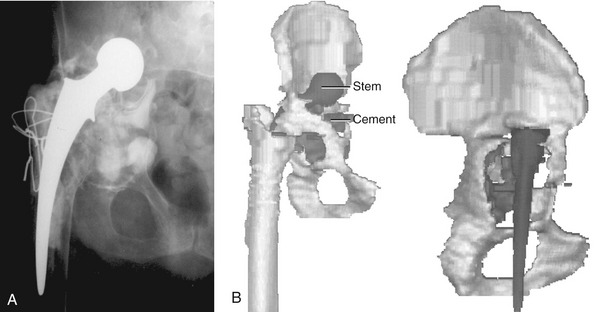

The iliac and ischial flanges contain multiple rows of screw holes for 6.5-mm screws. Five or six screw holes in the ischial flange are preferred because this area has proven to be the most common site of fixation loss. Two rows of three or four screw holes have proven sufficient for fixation of the iliac flange (Fig. 51-2). The pubic flange is smaller in size and contains no screw holes.

The CTAC is best implanted through an extensile posterolateral approach with or without a trochanteric osteotomy. Care must be taken to protect the superior gluteal artery and nerve when the gluteus minimus and medius are elevated from the iliac wing. In patients with severe acetabular component protrusion, a retroperitoneal approach initially may be required to carefully free the iliac vasculature from the protruded acetabular component, followed by revision THA through a separate extensile posterolateral or transtrochanteric surgical approach (Fig. 51-3). The sciatic nerve is protected by extending the hip when the hamstring origin is cleared from the ischial tuberosity.